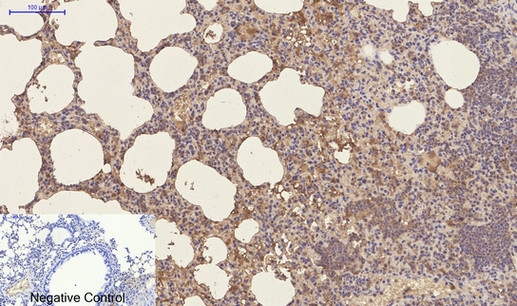

- Immunohistochemistry analysis of paraffin-embedded Human lung tissue using CD23 antibody. High-pressure and temperature Sodium Citrate pH 6.0 was used for antigen retrieval. Negative control was used by secondary antibody only.

- Immunohistochemistry analysis of paraffin-embedded mouse lung tissue using CD23 antibody.High-pressure and temperature Sodium Citrate pH 6.0 was used for antigen retrieval. Negative control was used by secondary antibody only.